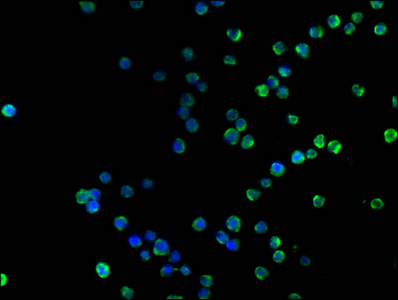

Immunofluorescence staining of Raji cells with CSB-MA004888A0m at 1:100, counter-stained with DAPI. The cells were blocked in 10% normal Goat Serum and then incubated with the primary antibody overnight at 4°C. The secondary antibody was Alexa Fluor 488-congugated AffiniPure Goat Anti-Mouse IgG(H+L).